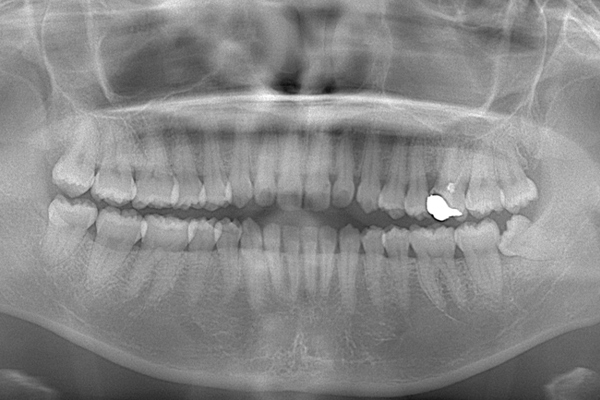

検査時のレントゲン写真です。

下顎の親知らずは右下のみはえています。まっすぐはえていますが、前の歯よりも低い位置にあるので、磨くのが難しそうです。舌側の歯茎がかぶっているのがみてとれます。

上顎の親知らずは頬の方を向いてはえています。こういうった親知らずはやはり磨くのがとても難しいです。